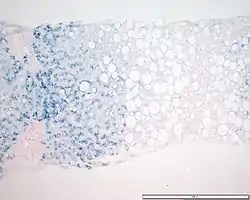

![]() Preparación teñida con azul de Prusia para revelar depósitos de hierro; muestra un patrón típico de acumulación de hierro de la hemocromatosis genética en heterocigosis (véase coloración azulada al ampliar la imagen). | ||